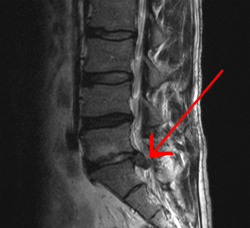

If you recall we covered something called a tethered spinal cord, cauda equina syndrome is somewhat similar, but as the name implies, it affects the cauda equina and not the spinal cord itself. Technically the disorder means that the cauda equina becomes damaged. This doesn’t have to happen by tethering. However, one of the more common causes is spinal disk herniation, which then causes pressure to be applied to the cauda equina, not unlike what happens when you have a tethered spinal cord. Below is an image (red arrow) that shows what a herniated disk looks like, which also helps explain why it can cause this type of damage.

Disk herniation (red arrow) is typically caused when the spinal column compresses and the membrane around the disk ruptures.